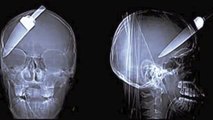

11 Most Bizarre Things Found in Humans

Bizarre things discovered in the human body: cellphone found in a man's throat